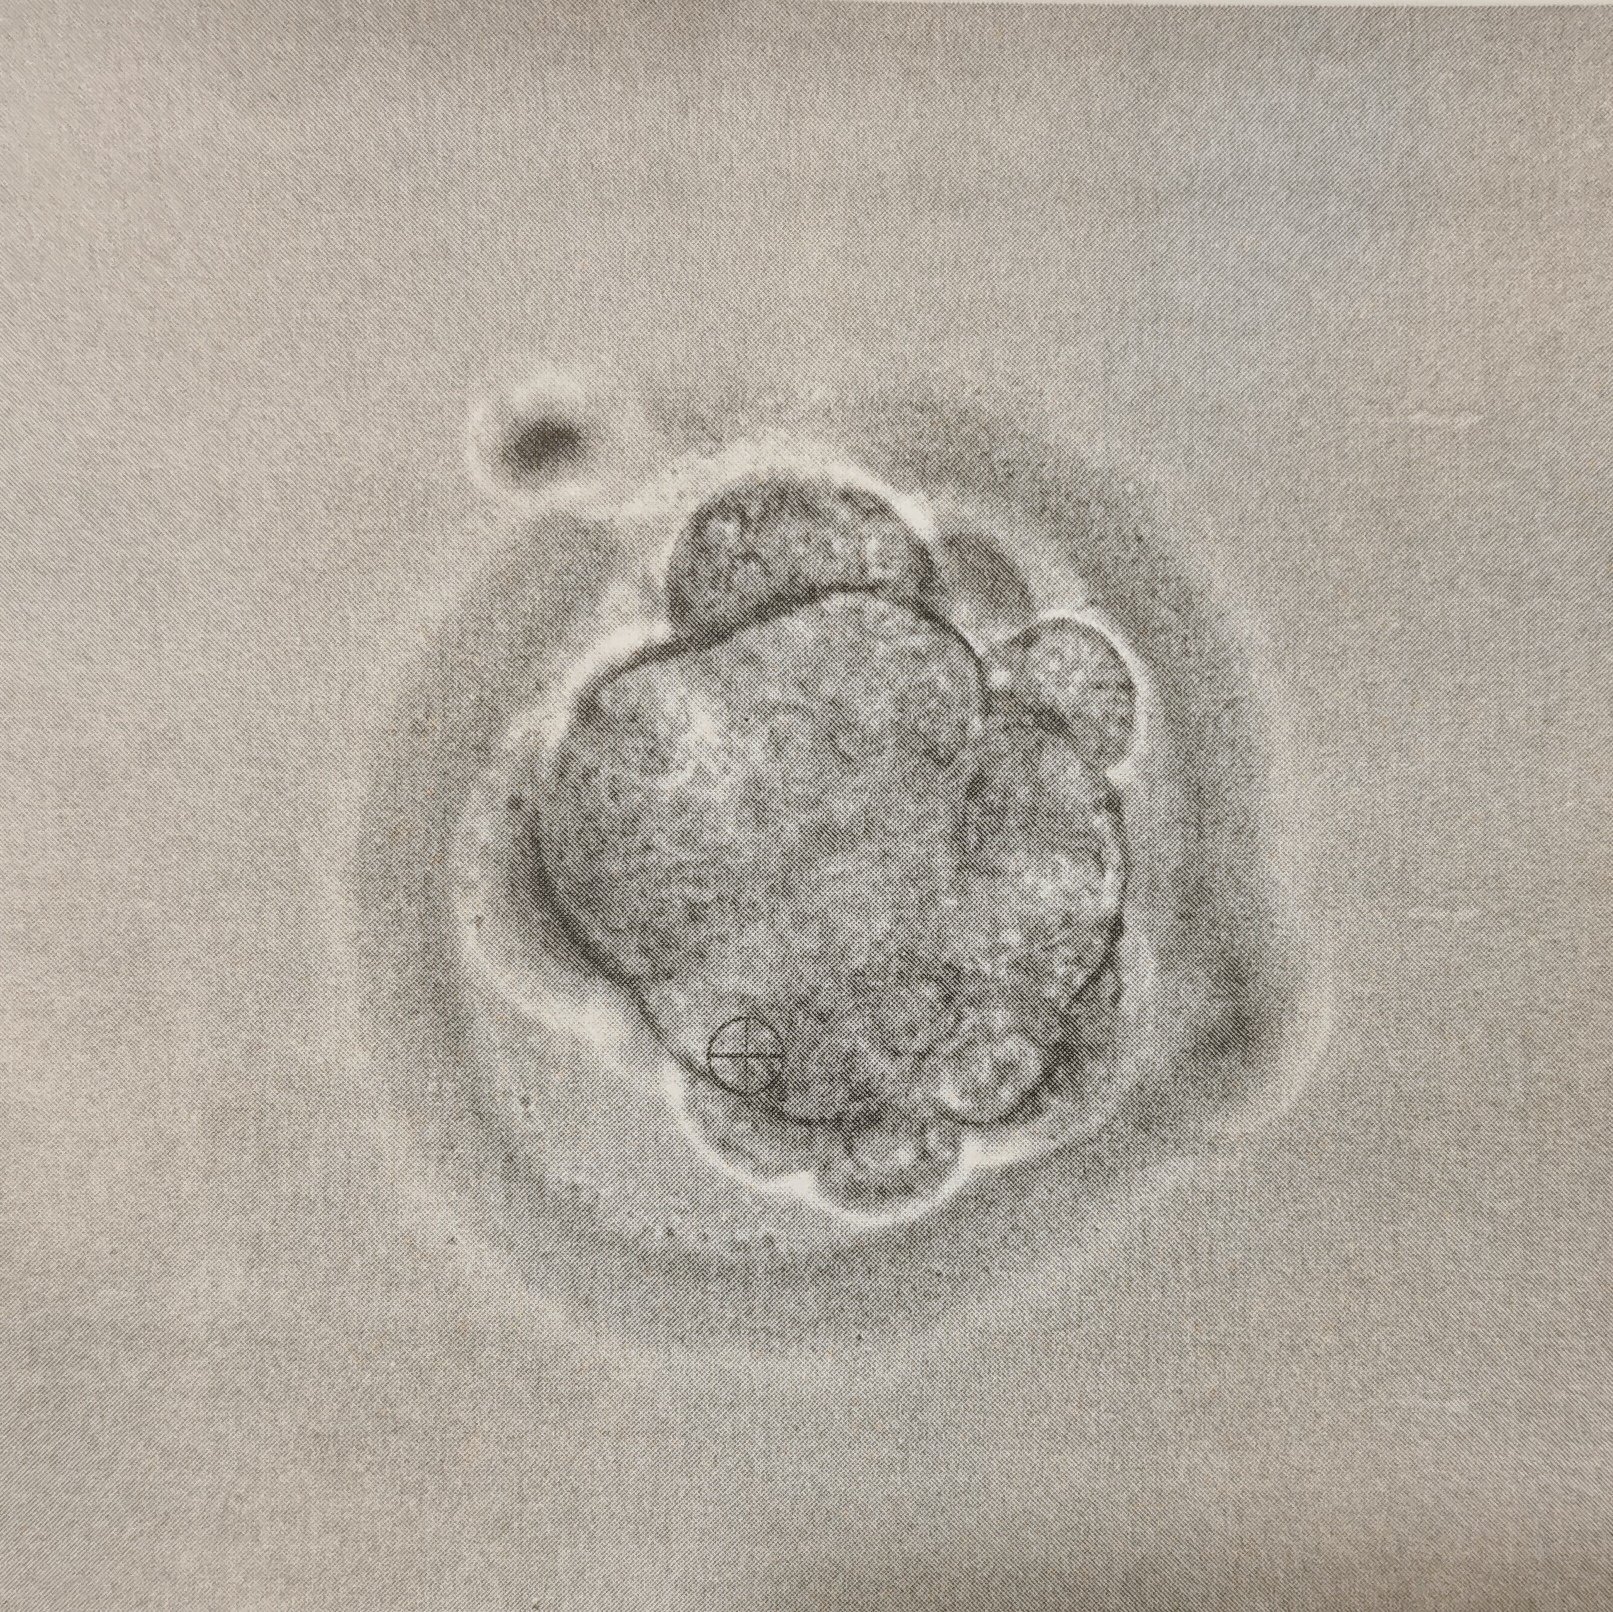

След трансфер на третия ден, ембрионът продължава да се развива. На ден 1, той преминава от 6-8 клетъчен ембрион в стадий морул. На ден 2 клетките на морул продължават да се делят, развивайки се до бластоцист. На ден 3 обвивката на бластоциста започва да се пука, а на ден 4 бластоцистът продължава да се освобождава от обвивката си и започва да се закача към маточната стена. На ден 5 бластоцистът се закача все по-дълбоко и започва имплантацията. Следващите дни са свързани с продължаваща имплантация и развитие на клетки, които впоследствие ще се превърнат в плацента и фетус.

След трансфер на пети ден, обвивката на бластоциста започва да се пука на шести ден. На седмия ден, бластоцистът продължава да се освобождава от обвивката си и започва да се закача към маточната стена. На осмия ден, бластоцистът се закача все по-дълбоко и започва имплантацията. На деветия ден, имплантацията продължава, а на десетия ден тя е завършена, като клетките, които в последствие ще се превърнат в плацента и фетус, вече са започнали да се развиват.